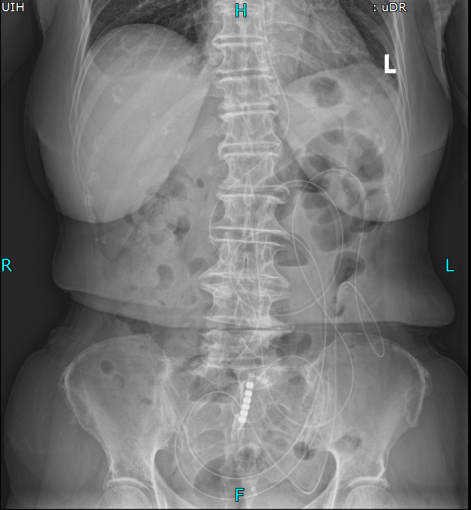

置入导管后肠梗阻明显减轻

考虑到王奶奶疼痛难忍、无法移动,普外科团队直接将胃镜设备推至病房床边,不到10分钟就完成了肠梗阻导管置入术。这根长达280cm的特殊导管不仅快速缓解了王奶奶的胀痛,还为后续治疗争取了关键时间,也为手术提供了安全保障。

肠梗阻导管置入后,王奶奶的腹痛腹胀明显缓解,叶晋生迅速启动多学科会诊(MDT),麻醉科、ICU、消化科等专家,综合评估王奶奶的高龄、高血压、既往手术史等多重风险,最终确定手术方案:腹腔镜下肠粘连松解术+小肠部分切除术。